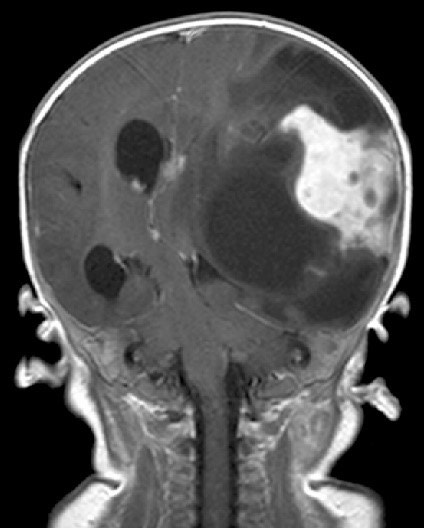

3809. У девочки 1,3 года с жалобами на острую правостороннюю моторную слабость необходимо дифференцировать рентгенологическую картину с